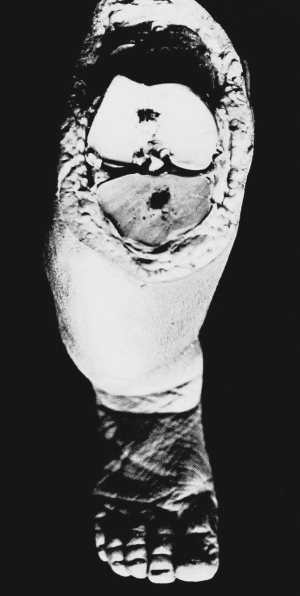

Plate showing Centre of Ossification in the Lower Epiphysi of PAGE

Femur in full time Fœtus To face 64

A plate, showing the centre of ossification in the lower epiphysis of the femur in a full time fœtus, has been introduced at the last moment, and will be found opposite page 64. References to the subject may also be found on pages 33 and 174.